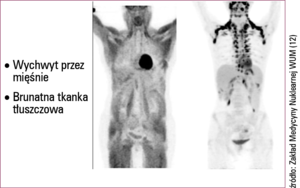

PET jest badaniem czynnościowym, umożliwia ocenę określonej funkcji komórki, dlatego od pytania postawionego przez onkologa zależy przebieg badania i wybór odpowiedniego radiofarmaceutyku.

Badanie PET jest obecnie jednym z ważniejszych narzędzi stosowanych w diagnostyce schorzeń onkologicznych. Badanie to jest symbolem nowoczesnej diagnostyki onkologicznej. Metoda polega na podaniu choremu odpowiedniej substancji chemicznej wyznakowanej emiterem promieniowania pozytonowego, biorącej udział w określonym procesie biologicznym. Pozyton, w bliskim sąsiedztwie miejsca emisji, ulega interakcji z elektronem (anihilacji). W wyniku tej reakcji powstaje promieniowanie gamma monitorowane przez aparat. Ponieważ w wyniku anihilacji powstają dwa promienie gamma biegnące w dwóch przeciwnych kierunkach, w rejestracji wykorzystuje się zjawisko koincydencji: dane zdarzenie jest rejestrowane, jeśli dwa przeciwlegle leżące detektory zostaną pobudzone w tym samym czasie. Dzięki temu uzyskiwane obrazy charakteryzują się znacznie lepszą rozdzielczością. Możliwe jest znaczne ograniczenie promieniowania rozproszonego w eń onkologicznych. Badanie to jest symbolem nowoczesnej diagnostyki onkologicznej. Metoda polega na podaniu choremu odpowiedniej substancji chemicznej wyznakowanej emiterem promieniowania pozytonowego, biorącej udział w określonym procesie biologicznym. Pozyton, w bliskim sąsiedztwie miejsca emisji, ulega interakcji z elektronem (anihilacji). W wyniku tej reakcji powstaje promieniowanie gamma monitorowane przez aparat. Ponieważ w wyniku anihilacji powstają dwa promienie gamma biegnące w dwóch przeciwnych kierunkach, w rejestracji wykorzystuje się zjawisko koincydencji: dane zdarzenie jest rejestrowane, jeśli dwa przeciwlegle leżące detektory zostaną pobudzone w tym samym czasie. Dzięki temu uzyskiwane obrazy charakteryzują się znacznie lepszą rozdzielczością. Możliwe jest znaczne ograniczenie promieniowania rozproszonego w tworzeniu ostatecznego obrazu scyntygraficznego.

Kamieniem milowym w rozwoju tej metody było wprowadzenie urządzeń hybrydowych. Obecnie praktycznie wszystkie dostępne skanery pozytonowej tomografii emisyjnej są urządzeniami hybrydowymi – PET/CT. Aparat składa się z wielorzędowego tomografu TK i gamma kamery PET. TK spełnia dwie podstawowe funkcje: